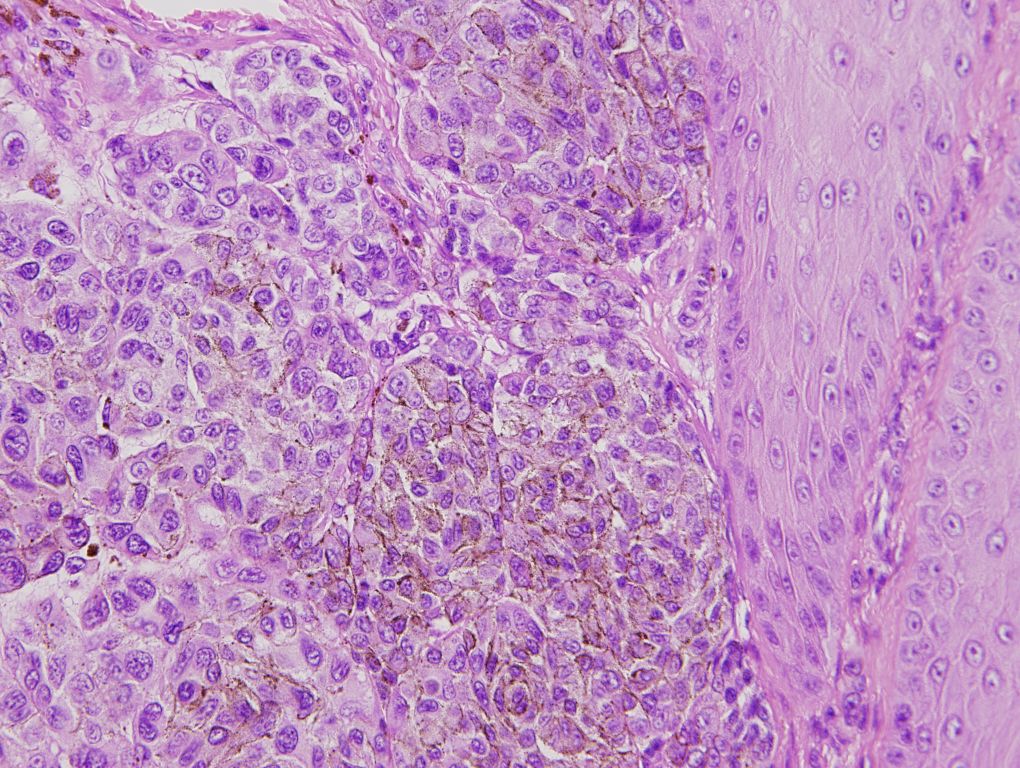

研究では、診療データを有効活用するために、診断や検査結果、治療成績の解析を行っています。また、臨床検体を用いて腫瘍微小環境などの解析も実施しています。

当グループが対象とする疾患は、皮膚、皮下に生じる腫瘍全般です。悪性黒色腫 (メラノーマ)、有棘細胞癌、乳房外パジェット病、メルケル細胞癌や基底細胞癌をはじめとした 皮膚がんのほか、血管肉腫、隆起性皮膚線維肉腫、明細胞肉腫、粘液線維肉腫、脂肪肉腫などの軟部肉腫、皮膚リンパ腫です。また、がんだけでなく、母斑細胞母斑(ほくろ)、 脂漏性角化症、脂肪腫や粉瘤などの良性腫瘍も治療しています。

病理診断については、皮膚病理を専門とする皮膚科医師が全ての症例の術前生検と切除後の標本の診断の確認と検討を行っています。診断が難しい症例は、病理診断科医師と定期的に検討会を行っています。